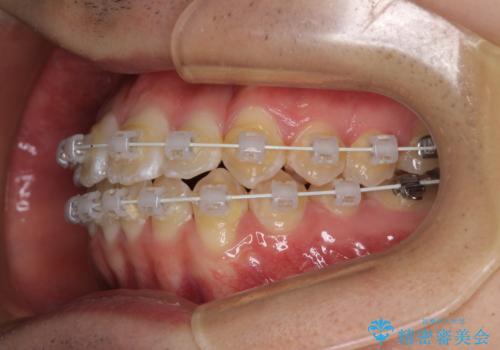

- 上下前歯のデコボコを気にして来院された患者様です。

ワイヤー矯正でもマウスピース矯正でも可能でしたが、短期間で、自身の手を煩わせることなく治療を行いたいとのことで、ワイヤー装置にて矯正治療を行うこととしました。

当初予定通り、1年間で治療を終えることができました。